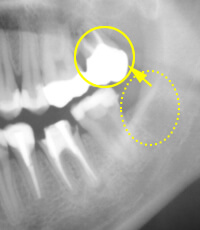

歯の移植・再植

根の先の病巣が大きいなど、状態が良くない歯の場合、根の治療のみでは治癒は期待できず、やむなく抜歯になってしまうケースがあります。 その場合、他の歯(例えば、親知らず)を抜いた部分に戻す移植法と、患歯を1度抜いて治療して戻す再植法があります。

■再植法